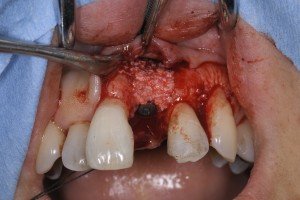

このケースも裂開がありましたので、ボーンチップとBi0-ossとBio-guideでインプラント埋入と同時法のGBR(骨造成)を行いました。

フィクスチャー表面に自家骨、その上にDBBMでカバーします。

さらにバイオガイドで被覆します。